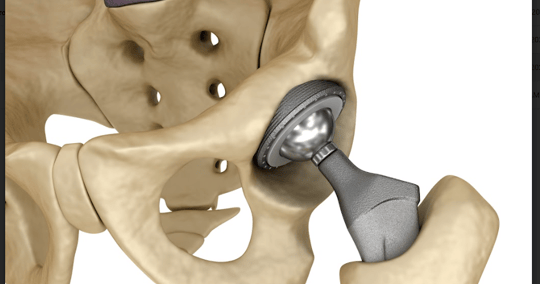

Achieve 2X faster AM production speeds even for large joint applications